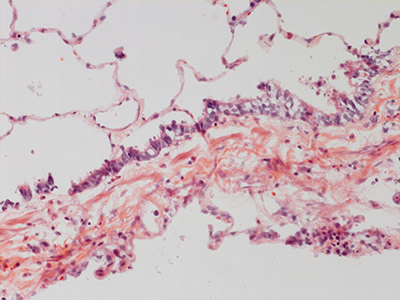

31 Year Old Adult Human Lung DD034L H&E